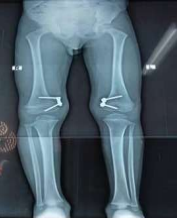

Figure 5